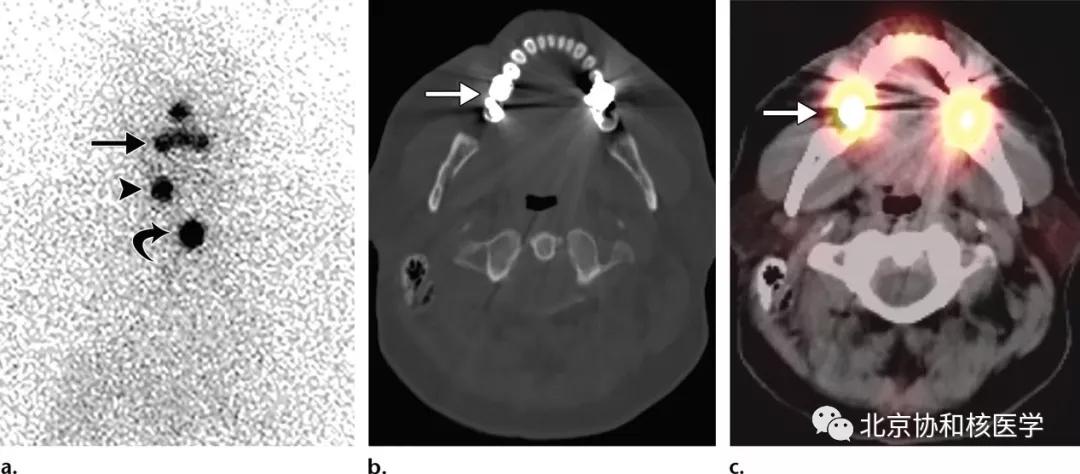

鼻腔脓肿所致碘摄取,其下方可见颈部残余甲状腺:

鼻腔息肉所致碘摄取,同时可见颈部残余甲状腺组织: